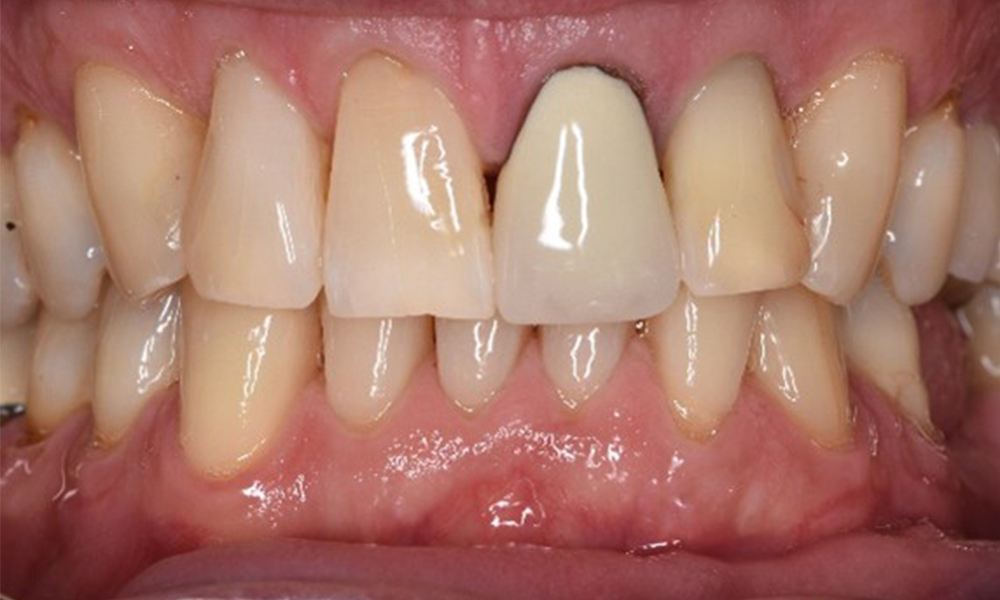

Casi di pazienti secondo l'IPCI seguenti studi di casi servono a mostrare l'interazione tra i fattori di bisogno e di rischio definiti per l'IPC così come gli effetti dei singoli fattori*. La paziente diabetica con una buona igiene oraleUna paziente diabetica di 51 anni con una buona igiene orale si presenta per una seduta di prevenzione. I valori di glicemia sono stabili con HbA1c = 6,2%, per cui si ritiene che la sua condizione possa essere sufficientemente gestita con la metformina (un farmaco per il trattamento del diabete). La paziente non presenta restauri esistenti o precedenti patologie orali. Sulla base dei referti disponibili si può constatare una gengivite nonostante una condizione altrimenti stabile. di più Case presentation: Complex Dental Prosthesis ManagementThe direct relationship between intraoral and general health, as well as the bidirectional influence that they may have on one another, is well-known (1,2). It is absolutely essential to consider both factors when planning preventive intraoral measures and treatment in the dental practice. The primary objective is the maintenance of patient health and quality of life from both dental and medical perspectives. more The (orally) healthy patient with implantsIn the medical history, the 55-year-old patient states that he has no systemic disease and is not taking any medication. The patient’s lifestyle is similarly unremarkable. The patient has a few tooth restorations and two implants (2nd and 4th quadrants). On the basis of current findings, gingivitis is identified in an otherwise stable periodontal condition on the reduced periodontium (stage III, grade A). more The healthy patient with pre-existing periodontal disease & peri-implantitisA 52-year-old patient presents at a preventive care session. The patient has no systemic disease and is not taking any medication. He has had various dental treatments and also has two active carious lesions. In addition, the patient has four implants (2nd, 3rd and 4th quadrants). He is revealed to have early periodontal disease (stage IV, grade B). His periodontal condition is stable; a probing depth of Probing depths (ST) of 5 mm is only evident at the implant in region 36. Gingivitis is also identified. more The Diabetic Patient with Pre-Existing PeriodontitisThis case report of a 52-year-old male with type 2 diabetes and periodontitis emphasizes personalized preventive measures and periodontal health maintenance to manage the moderate disease progression risk. more The 28-Year-Old Cigarette Smoker with Dental Erosions28-year-old patient, smoker, with erosions. The bidirectional relationship between oral and general medical health is very well known. It is no longer sufficient – and arguably even old-fashioned – to consider intraoral conditions in isolation. In order to create a personalized, case-specific preventive and patient profile, it is essential to take a detailed medical history and perform diligent examination of the general medical and intraoral health, as well as considering the two in combination. more Il paziente affetto da endocardite con lesioni cariose attiveIl paziente ha 39 anni e in passato è stato sottoposto ad un intervento per la sostituzione della valvola aortica dovuta a insufficienza valvolare ed endocardite. Assume regolarmente l'ASS 100 come anticoagulante. Per quel che riguarda lo stile di vita, il regime alimentare seguito dal paziente è classificato come “dieta che favorisce la formazione della carie”, per via del consumo regolare di cibi ad alto contenuto di zuccheri e dei sei-sette pasti consumati al giorno. La salute orale del paziente indica un rischio moderato di carie, con lesioni attive. Il rischio di parodontite è basso, tuttavia il paziente è affetto da gengivite. Si formulano quindi i seguenti consigli per il trattamento di profilassi. di più Il paziente trapiantato con iperplasia gengivaleSi presenta un paziente di 71 anni che ha subito un trapianto di reni e con anamnesi di ipertonia (ipertensione). Considerata la sua storia clinica, serve una terapia a lungo termine con ciclosporina che ha un effetto immunosoppressivo e amlodipina che è specifica contro l'ipertensione. Il paziente riporta anche gengive sensibili e sanguinanti. Per quanto riguarda invece lo stato di salute orale, il paziente ha un restauro, presenta un'iperplasia gengivale marcata, una parodontite allo stadio II, grado B con tasche attive e un'iniziale carie radicolare al dente 22 e in più mancano otto denti. Dalla valutazione del rischio di carie si evince un rischio moderato di carie (API 60). Per la seduta di profilassi si possono formulare i seguenti consigli per il trattamento. di più La paziente sana con precedente patologia parodontaleQuesta paziente di 68 anni non presenta alcuna patologia precedente né segue alcuna terapia che possano ritenersi rilevanti dal punto di vista odontoiatrico, e il suo stile di vita non comporta alcun rischio particolare. La paziente ha due impianti (3° quadrante, da cinque anni) e una precedente patologia parodontale (parodontite allo stadio IV, grado B) con perdita del dente. Al momento le condizioni parodontali sono stabili, tuttavia la parodontite aumenta in misura significativa le complicazioni biologiche degli impianti e c'è dunque il rischio di perdita dell'impianto (21). Per la seduta di profilassi si possono formulare quattro consigli. di più